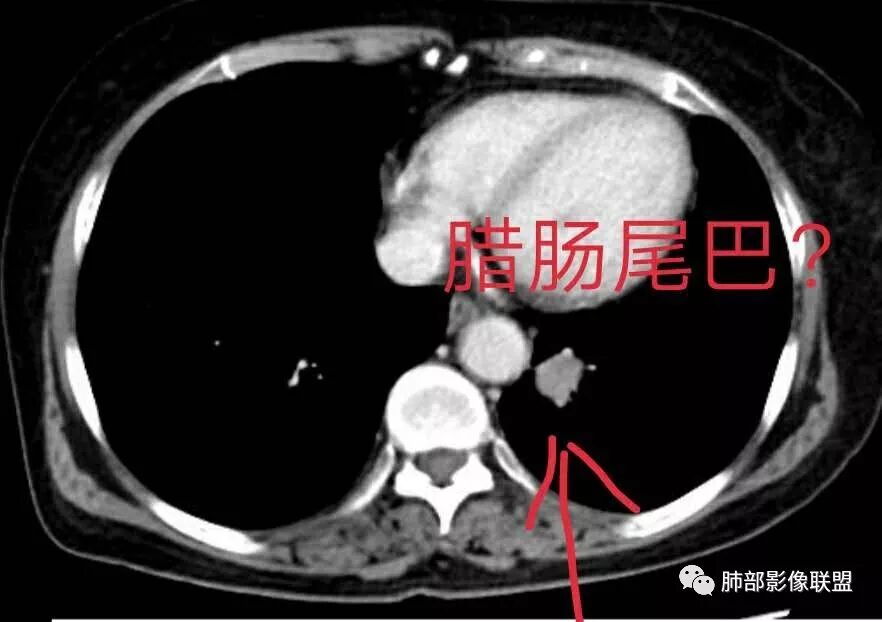

Yiren  Sishui(厶水伊人):

这个算不算腊肠尾巴?

宇宙星空:小细胞还是支气管堵塞的多吧。那个好像是血管吧。